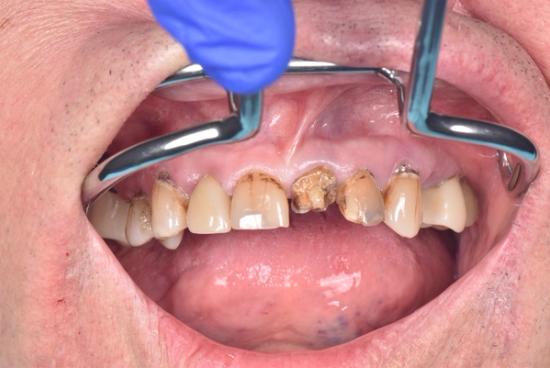

Before Photo